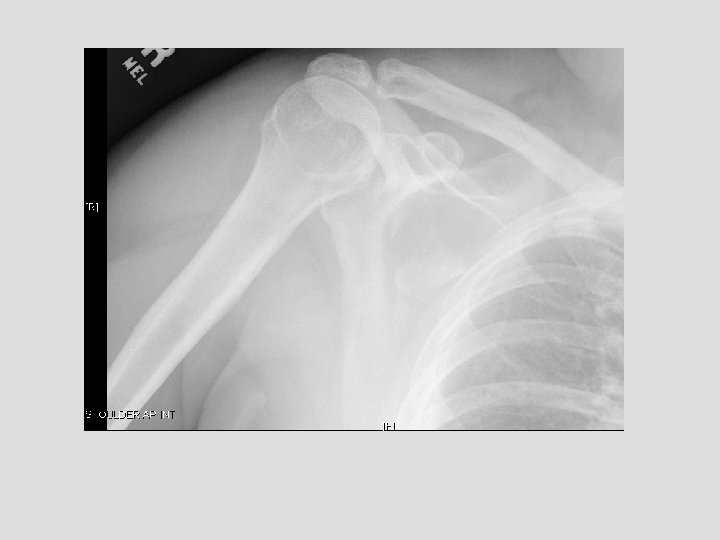

Findings and Differentials Findings: On the CXR, there is a piece of bone overlying

Findings and Differentials Findings: On the CXR, there is a piece of bone overlying the right scapula, which could easily be missed. The follow-up shoulder series and CT more clearly demonstrate a fracture. The CT clearly shows the donor site to be the coracoid process. Differentials: • Coracoid avulsion fracture